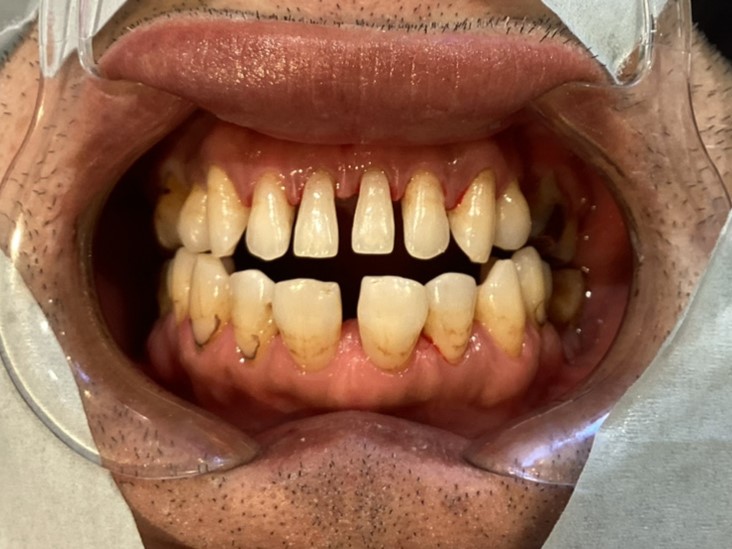

歯の汚れ・ヤニトリについて

歯の汚れって色々ありますよね 今回は着色をとる方法についていろいろお話していきます。 着色といってもたばこのヤニだったり、紅茶、カレーなど色素が濃いものによって歯に着色がつくことがあるります。 今回あげた写真は「エアフロ […]